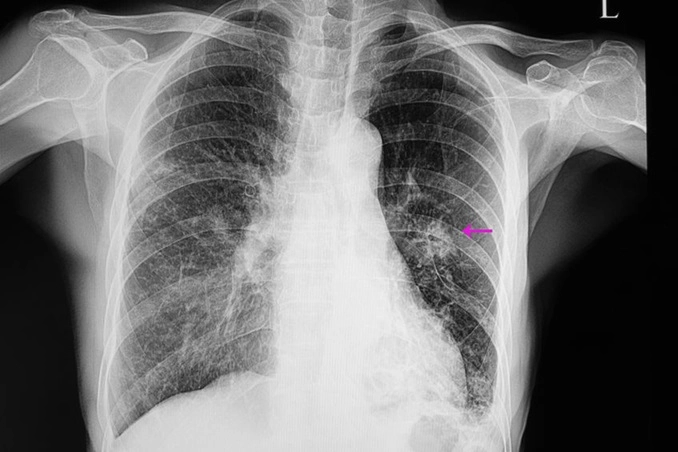

Akciğer kanseri şikayete yol açtığında sıklıkla ileri evrede oluyor. Geç teşhis edilmesinin nedeni ise kanserin çoğunlukla uzun süre belirti vermemesi veya öksürük gibi yakınmaların sigaraya bağlanarak önemsenmemesi. Ayrıca yoğun sigara kullanan hastalarda tarama yöntemlerinin olmaması da geç teşhisin bir diğer sebebini oluşturuyor. Erken evrede çoğunlukla belirti vermemesi nedeniyle bu dönemde ancak rastlantısal çekilen bir görüntüleme yöntemi sonrasında fark ediliyor. İleri evrelerde ise uzun süreli öksürük, kan tükürme, nefes darlığı, boyunda şişme, göğüs bölgesinde ağrı, hırıltı veya ses kısıklığı gibi belirtilerle kendini belli ediyor. Tıbbi Onkoloji Uzmanı Prof. Dr. Faysal Dane, bu tür belirtilerin mutlaka akciğer kanseri yönünden tetkik edilmesi gerektiğine işaret ederek, “Akciğer grafisi bazı büyük kitleleri veya sıvı toplanmasını gösterebilmektedir. Şüphe olan hastalarda düşük doz bigisayarlı tomografi çekilmesi en uygun olan yöntemdir. Asıl teşhis ise görülen kitleden biyopsi yapılarak alınan numunenin mikroskop altında incelenmesiyle konulmaktadır” diyor.